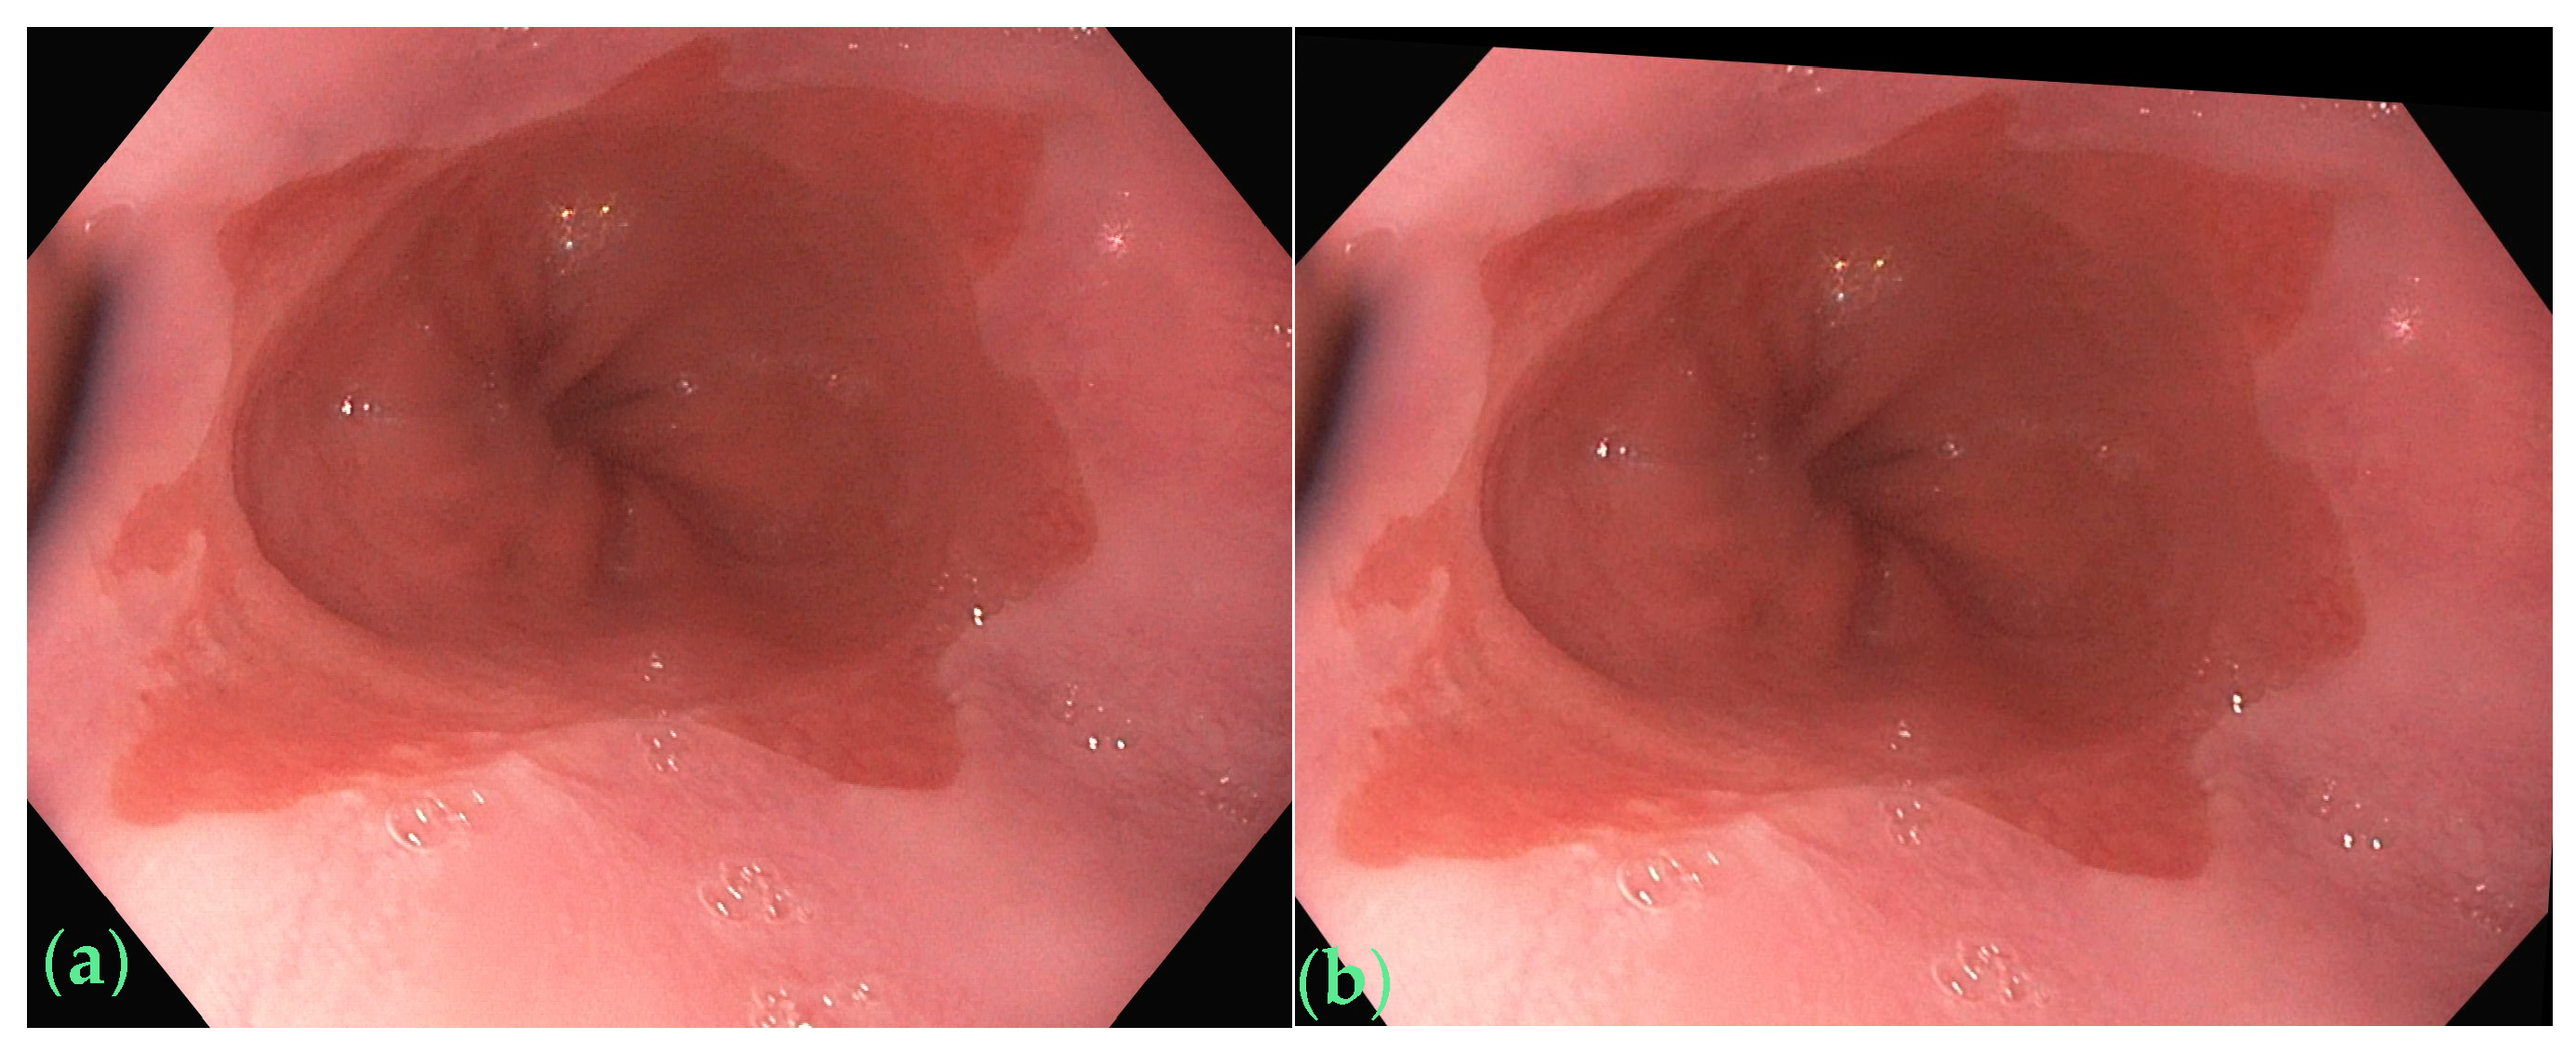

2.1. Raw Images and the Annotation Method